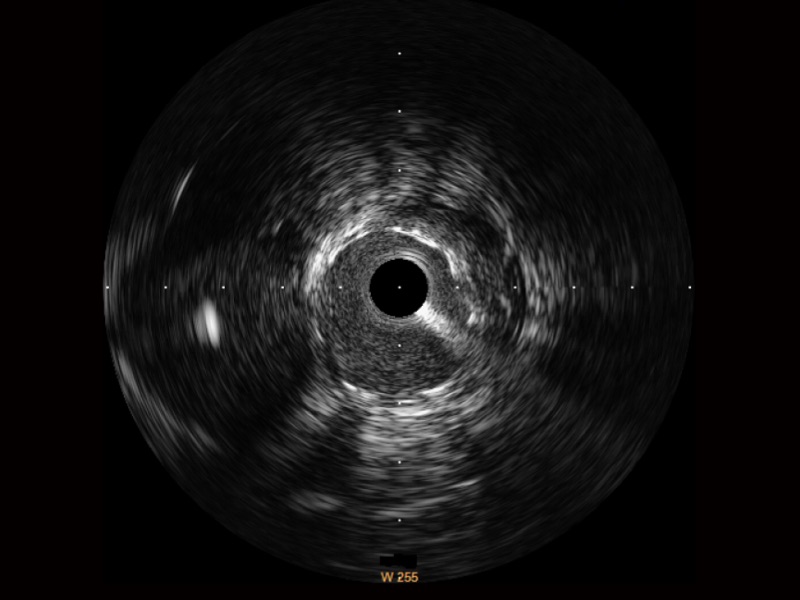

• 传统IVUS图像

对比传统IVUS导管成像,诸侯快讯官网宽频IVUS图像的近场支架梁显影更细腻,远场中膜外血管仍清晰可辨,兼顾远中近,兼顾分辨力与穿透深度